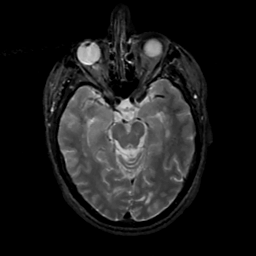

MR Study #15, June 9, 1991 -- Slice #19